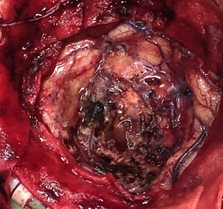

脑膜瘤切除术

王xx,女,52岁

患者因“间断性头晕头痛2个月”入院

诊断:右侧额部脑膜瘤

入院:神志清楚,双侧瞳孔圆形等大,直径3.0 mm,对光反射灵敏,左侧肢体肌力III级、右侧肢体肌力正常,肌张力正常。

脑膜瘤完整切除                       切除的完整肿瘤